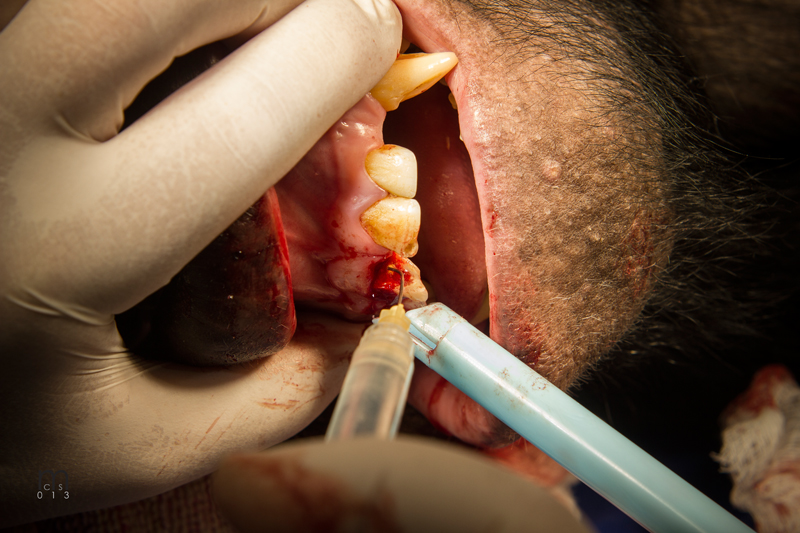

Incision on crest of ridge.

Luxator technique utilized to remove residual roots.

556 surgical bur used to remove approximately 2mm. of alveolar bone surrounding each root ("ditching".)